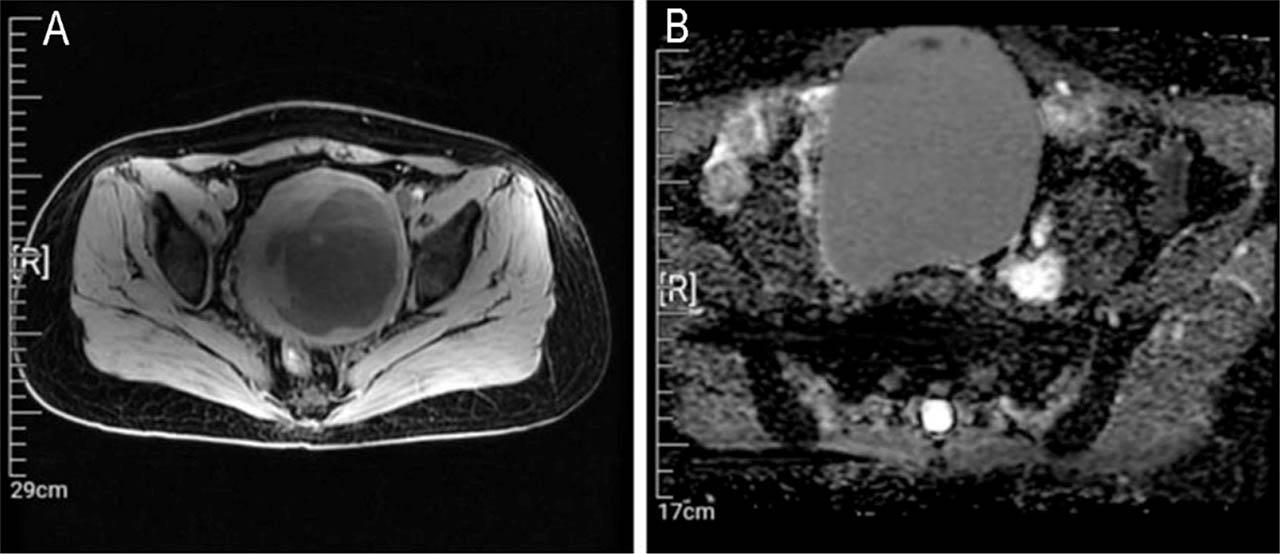

No regular ultrasound reexamination was performed until April 2021, and the results showed an enlarged and morphologically abnormal uterus, a mixed uneven echogenic mass at the posterior wall of the uterus (101 mm × 85 mm, with 7 mm thick endometrium), and a dark cyst (109 mm × 93 mm) in the right adnexal area with dense punctate echo, suggesting suspected uterine myoma with liquefaction and a suspected chocolate cyst. Abdominal computed tomography showed lesions in the pelvis and uterus (Figure 1). A pelvic magnetic resonance imaging examination suggested a suspected myoma cyst with malignant potential in the uterus and a suspected cystadenoma in the right adnexal area (Figure 2).

Figure 2

Magnetic resonance imaging and macroscopic findings. (A) T2-weighted image and (B) diffusion-weighted image depicting a high signal intensity in the uterine fibroid.